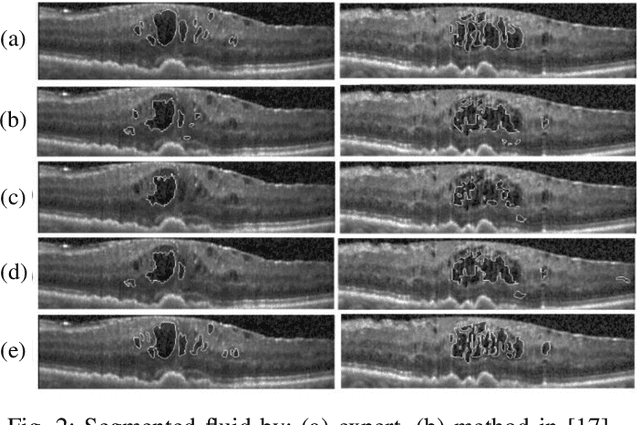

Abstract:Optical coherence tomography (OCT) as retina imaging technology is currently used by ophthalmologist as a non-invasive and non-contact method for diagnosis of agerelated degeneration (AMD) and diabetic macular edema (DME) diseases. Fluid regions in OCT images reveal the main signs of AMD and DME. In this paper, an efficient and fast clustering in neutrosophic (NS) domain referred as neutrosophic C-means is adapted for fluid segmentation. For this task, a NCM cost function in NS domain is adapted for fluid segmentation and then optimized by gradient descend methods which leads to binary segmentation of OCT Bscans to fluid and tissue regions. The proposed method is evaluated in OCT datasets of subjects with DME abnormalities. Results showed that the proposed method outperforms existing fluid segmentation methods by 6% in dice coefficient and sensitivity criteria.